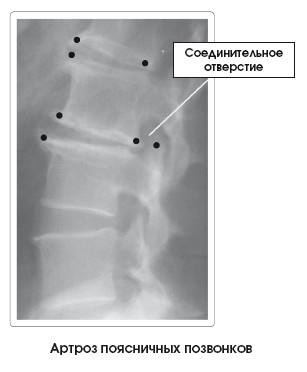

Костные деформации (), называемые остеофитами, шпорами или пиками костей, характеризуют данное заболевание. Они бывают выраженными в той или иной степени в зависимости от уровня прогрессирования артроза. В зависимости от локализации процесса, размера и потери объема диска могут раздражаться и повреждаться структуры мягких тканей, такие как нервы, проходящие через соединительные отверстия, или межпозвоночные диски.

С годами при сколиозе начинает развиваться артроз, вызванный нарушением функционирования суставов, сдавленных изгибом.

Для оценки состояния пациента применяют методы функциональной диагностики (рентген), объективного и субъективного обследования.